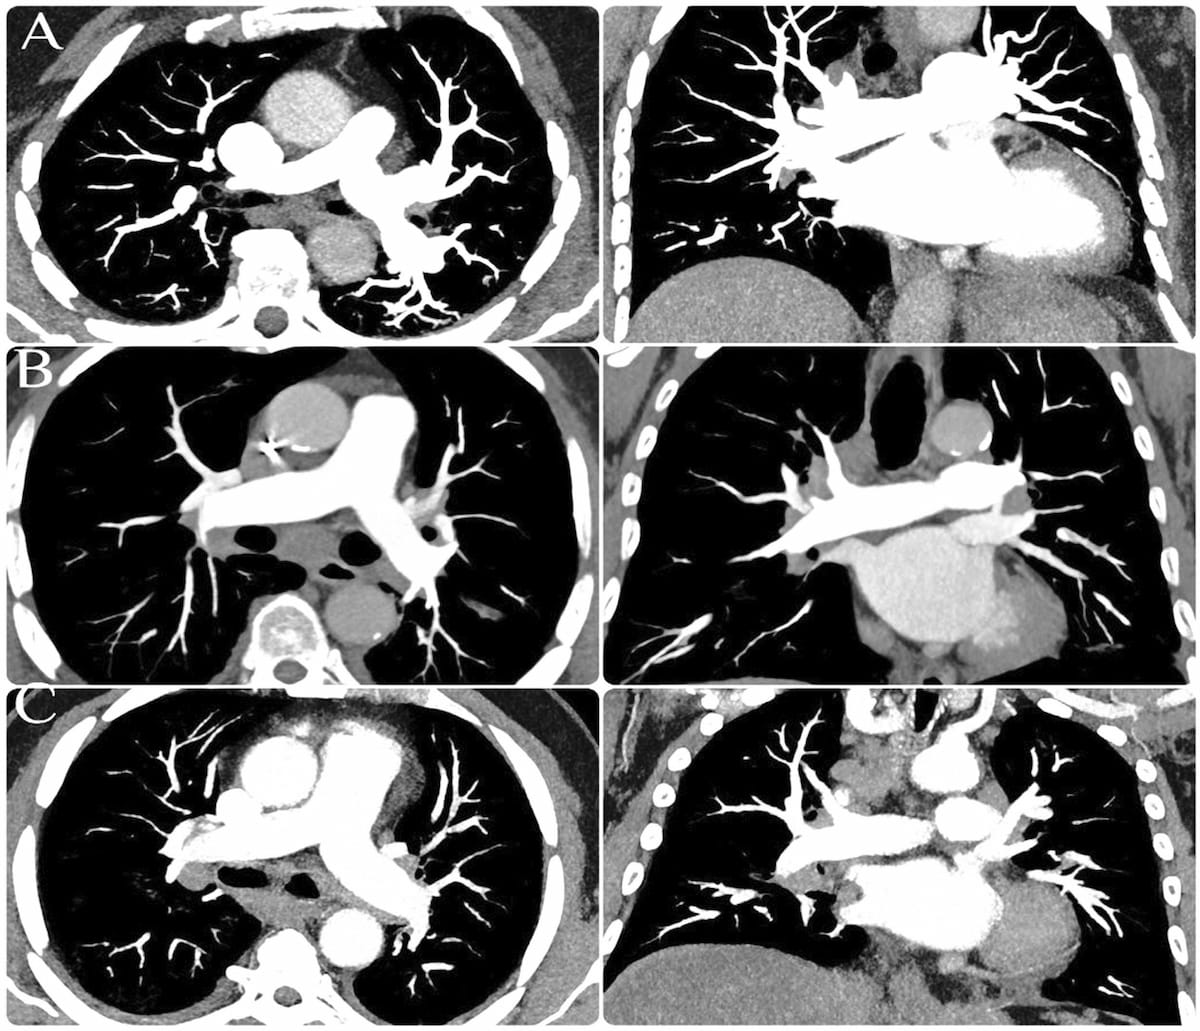

In a study cohort of patients undergoing pre-operative workup for transcatheter aortic valve replacement (TAVR), researchers found the use of photon-counting CT for ultra-high resolution coronary CT angiography had a 96 percent sensitivity rate and an 84 percent specificity rate for the detection of coronary artery disease (CAD).